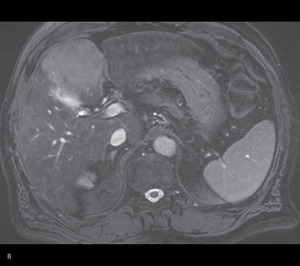

Badaniem mającym zadecydować o możliwości takiego leczenia był rezonans magnetyczny (MR) wykonany po czterech miesiącach od ustalenia rozpoznania (ryc. 1).

Rycina 1. Obraz MR przed leczeniem. (A) W projekcji osiowej widoczna zmiana w segmencie 6. (B) Na przekroju poprzecznym w segmencie 4 widoczna zmiana w okolicy pęcherzyka żółciowego

Stwierdzono powiększenie rozmiarów opisywanych wcześniej ognisk w wątrobie. Zmiana położona w segmencie 4a, w okolicy pęcherzyka żółciowego, osiągnęła wymiary 7,3 × 6 cm, a zmiana w segmencie 6 – 3 × 2 cm. W segmentach 5 i 7 uwidoczniono też nowe ogniska o średnicy poniżej 1 cm, nieulegające wzmocnieniu po podaniu środka cieniującego, dostrzegalne jedynie na obrazach T2-zależnych oraz w badaniu wykonanym metodą obrazowania dyfuzyjnego (DWI – diffusion-weighted imaging). Pozostały miąższ wątroby wykazywał cechy przebudowy marskiej. Nie uwidoczniono innych nieprawidłowości w obrębie jamy brzusznej, w tym powiększonych węzłów więzadła wątrobowo-dwunastniczego.